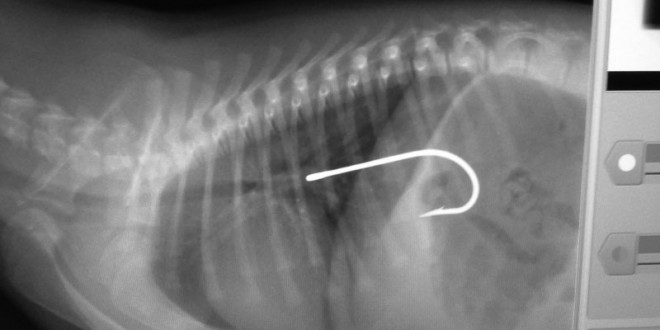

收好你的襪子、黃色小鴨跟燈泡!不然它們會出現在你家毛小孩胃裡!

fishinghook(1)